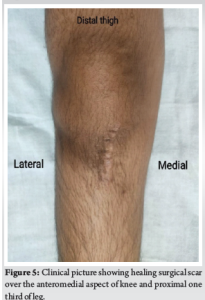

Surgical wound was found to be healed postoperatively (Fig. 5). Gentle right knee ROM was started on post-operative day 3. Initial range of movements of right knee were 0–70°. Partial weight bearing with right lower limb was started after 1 week. Complete weight bearing with right lower limb was started after 2 weeks. She achieved nearly full right knee range of movements till 110° by 8 weeks without any pain or restriction. She was rehabilitataed to her normal routine and activities with musculoskeletal tumor society score of 8. The patient was on 1-year follow-up. Follow-up plain radiograph at 3 months and 12 months shows that bone cement was intact without any local recurrence and lysis (Fig. 6a and b). She was able to perform normal activities with complete knee flexion (Fig. 6c) and no extensor lag (Fig. 6d and e). The patient was also able to do her recreational activities without any restrictions. The patient was adviced for a routine follow-up every 2 months to assess for any recurrence. Recurrence will be checked by clinical examination (to look for any new lump, tenderness around the surgical site) and radiological imaging such as X-ray (to look for any bony recurrence around the previous tumor site) and MRI scan (if suspected soft tissue involvement and to assess the extent of recurrence).